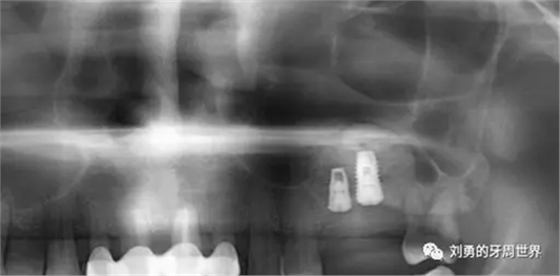

術(shù)后復(fù)查ct如下圖:

術(shù)后ct顯示種植體距離很近。植骨材料完整。